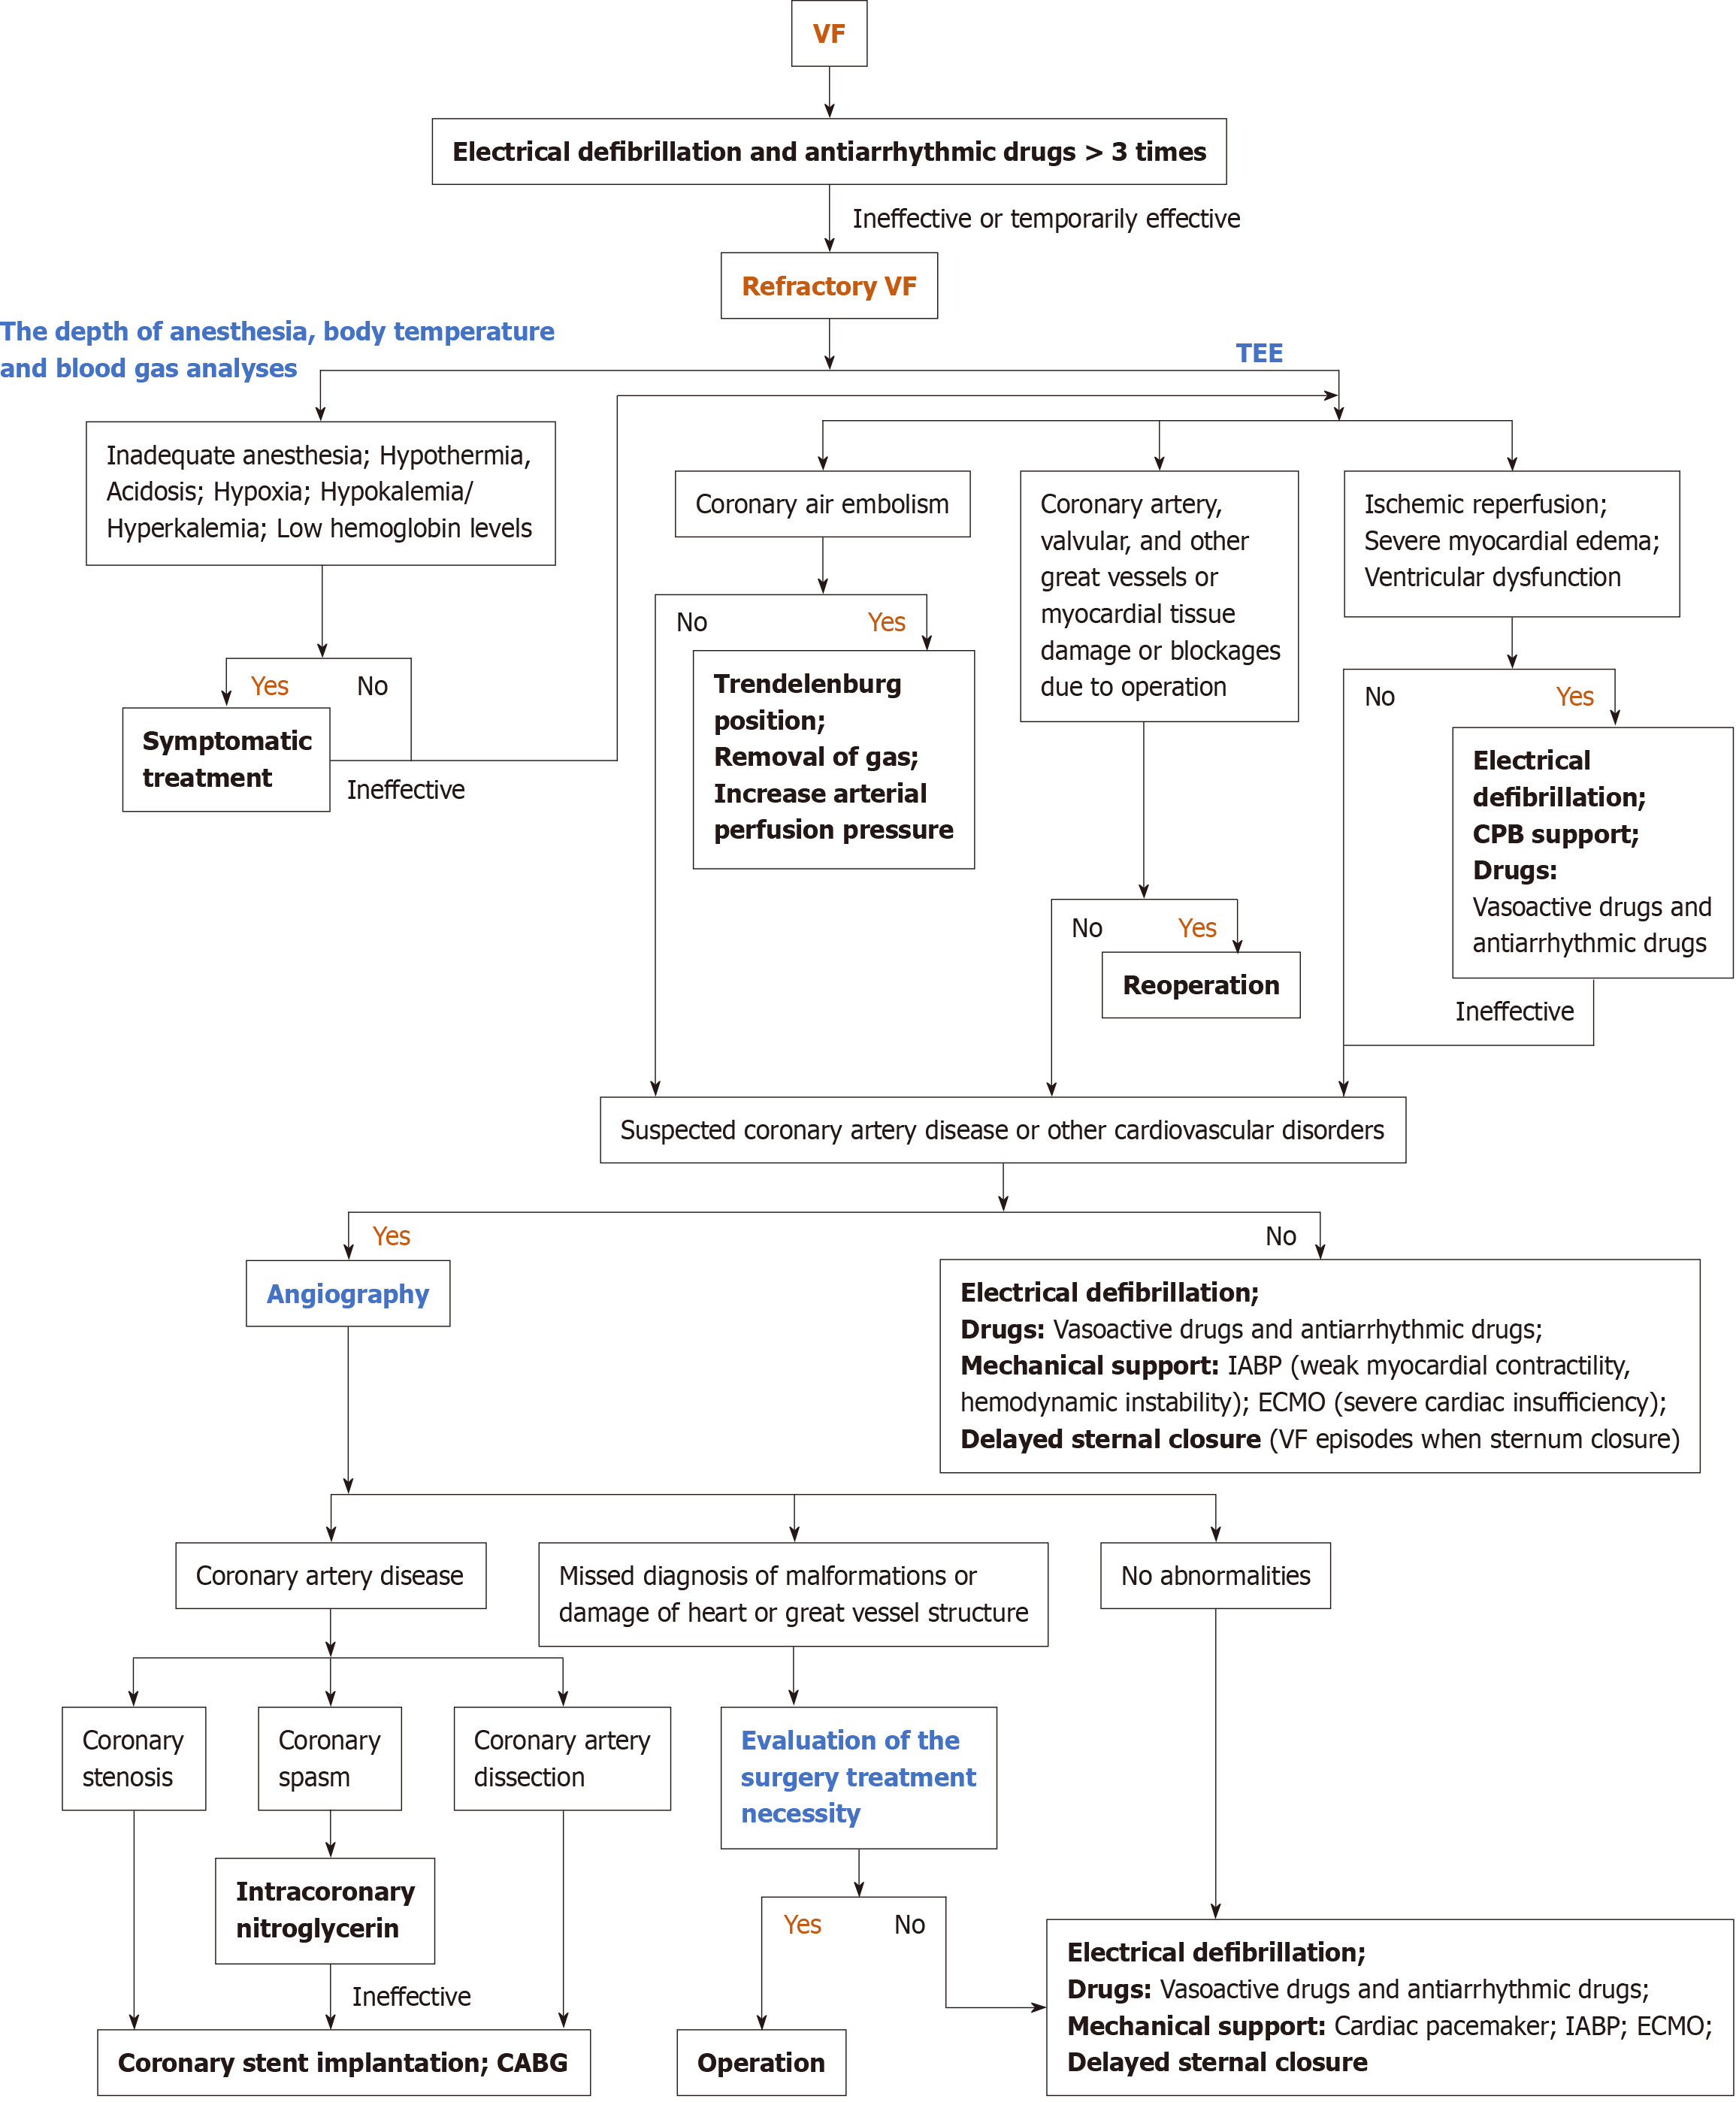

Core Tip: Refractory recurrent ventricular fibrillation (VF) is a severe ventricular arrhythmia in cardiac surgery. We present a rare case of refractory VF caused by coronary insufficiency during Bentall procedure. This report underscores the rarity and severity of coronary insufficiency following aortic root reconstruction. Additionally, we review causes and treatment of refractory VF in cardiac surgery and provide a clinical management protocol for refractory VF during cardiac surgery.

In fact, reperfusion VF is the most frequently reported and studied arrhythmia, occurring following the release of the ACC, with incidence rates ranging from 74% to 96%[3]. This complication has been attributed to the heterogeneous recovery of myocardial cells, ischemia-induced increases in reentry and automaticity, as well as the potential for reperfusion injury[4]. Preoperative severe myocardial damage and ventricular hypertrophy could increase the risk of reperfusion VF. Usually, electrical defibrillation, CPB support, antiarrhythmic drugs like lidocaine and amiodarone, and elevated coronary perfusion pressure assist in terminating reperfusion ventricular fibrillation. Interestingly, the efficacy of amiodarone or lidocaine in preventing reperfusion VF remains controversial[5,6]. In contrast, VF due to acidosis, hypoxia, potassium level, and coronary air embolism could be easily prevented, diagnosed, and treated. However, no clear expert consensus has been reached concerning the diagnostic and therapeutic strategies for refractory VF. Moreover, the research and reports of refractory VF are few in open heart surgery, and the treatment options for reference are limited accordingly. Jacob et al[7] reported a rare case of refractory VF induced by right coronary artery dissection after aortic valve replacement; CABG was undoubtedly the only effective method to treat radically refractory VF. Barr et al[8] employed delayed sternal closure to successfully resolve the repetitive VF that occurred upon chest closure in a 49-year-old male who underwent surgical repair of right coronary aneurysms. In addition, Extracorporeal membrane oxygenation (ECMO) is a viable therapeutic option for unexplained intractable VF, providing an opportunity for restoring the patient's cardiac function and figuring out the causes of VF[9]. In cardiac surgery, coronary artery spasm is rare but fatal and also serves as a cause of refractory VF[10]. Several predisposing factors have been proposed, including elevated catecholamine levels, local trauma, platelet release of vasoconstrictor mediators, respiratory alkalosis, hypothermia, and sympathoadrenergic stimulation[11]. Rahmouni and Ahmad et al[11,12] reported successful cases of post-cardiac valve coronary artery spasm treated with intracoronary nitroglycerin, implantable cardioverter-defibrillator (ICD), coronary stent implantation, and CABG, which are also therapeutic options for coronary spasm ICD[13,14]. Here, we summarize the diagnostic and therapeutic strategies for refractory VF during cardiac surgery based on previous studies and reports (Figure 3).

In summary, identifying the causes is crucial to treat refractory VF. In addition, once coronary insufficiency is confirmed or suspected in aortic root replacement surgery, CABG should be promptly performed.